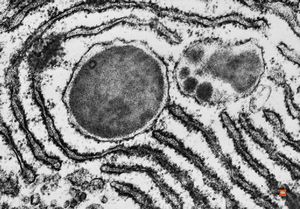

M,1y. | unusually cup-shaped mitochondria - plexus papilloma

M,1y. | intramitochondrial inclusion - plexus papilloma